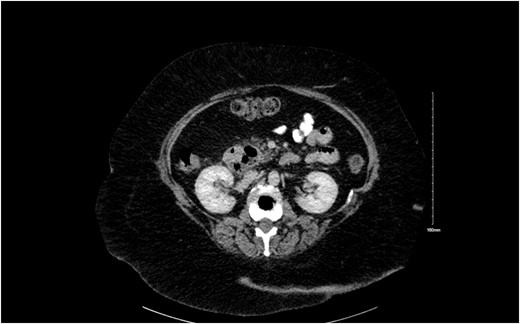

Duodenal diverticulum though rare usually occurs in 2–3 cm to ampulla of Vater. It is usually asymptomatic, but in 1%–2% patients can cause acute abdominal pain due to an extrinsic obstruction of common bile duct or pancreatic duct [3] as shown in Fig. 2.

(a) Principal bile duct normally between 4 and 8 mm in maximum diameter. (b) When a periampullary duodenal diverticulum is present, its extrinsic compression could enlarge periampullary duodenal diverticulum till obstructive jaundice.